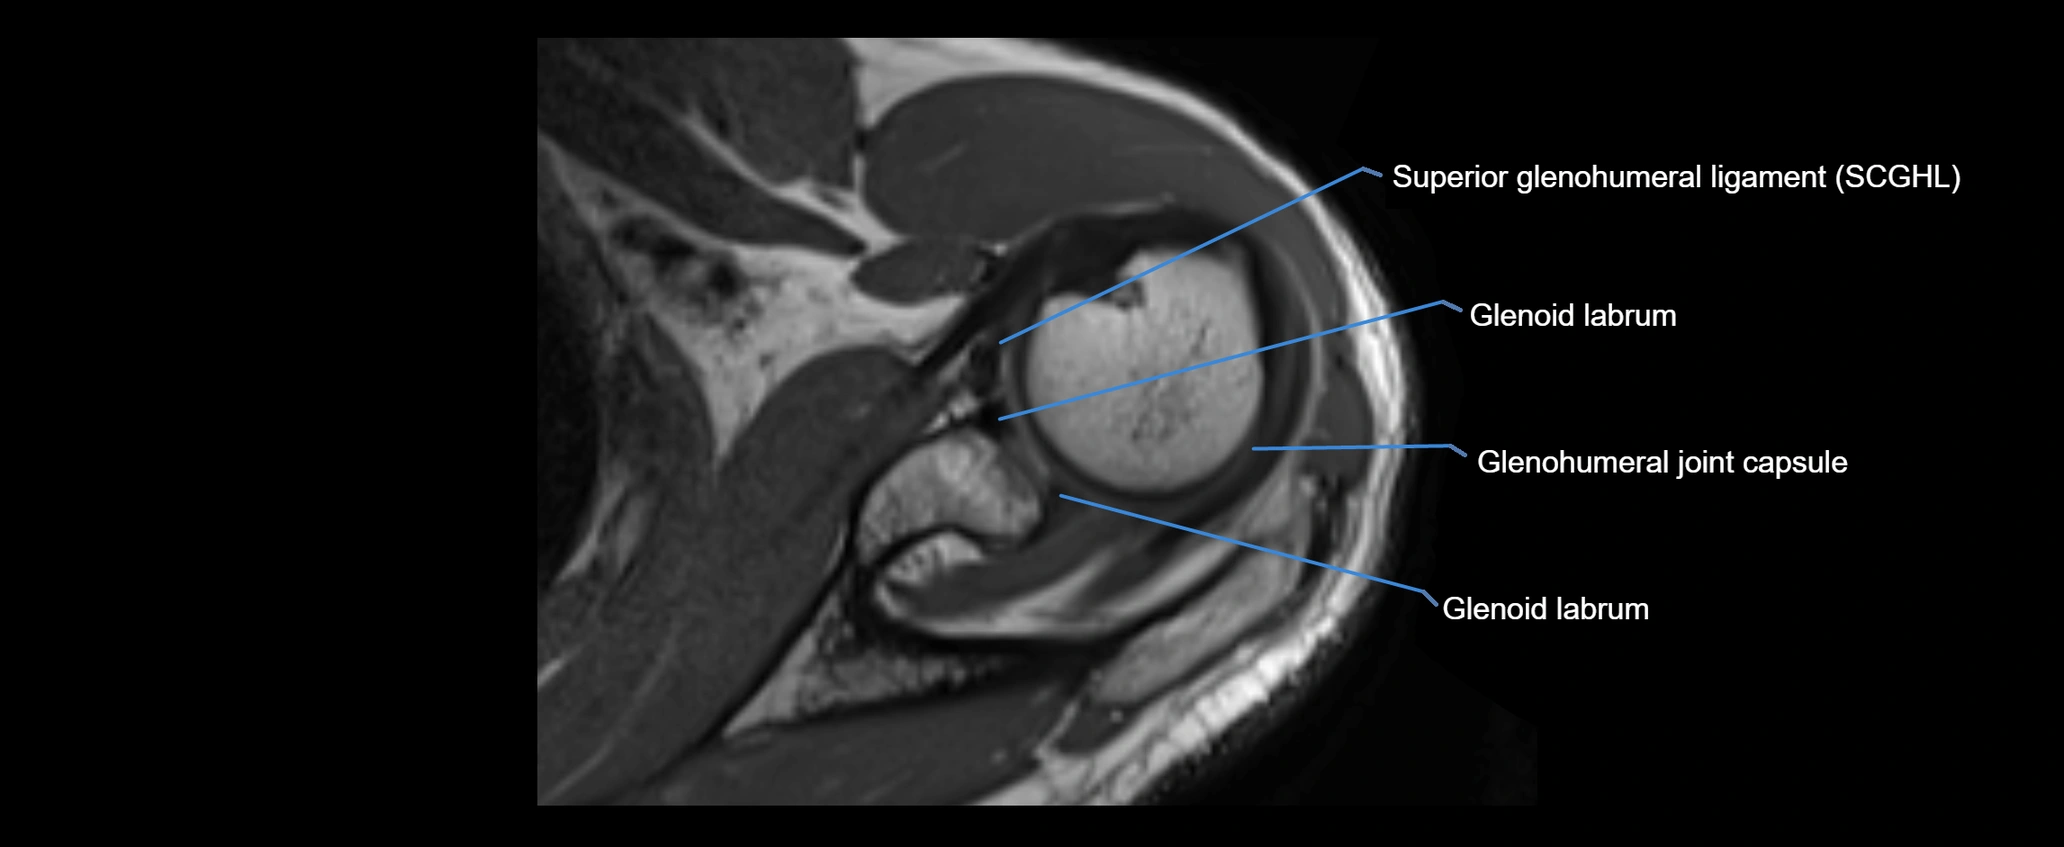

MRI images

image

MRI Appearance

• T2-weighted images:

• Normal ligament: Low signal, homogeneous.

• Partial tear or sprain: Focal hyperintensity or thickening.

• Complete tear: Discontinuity with fluid-bright gap between clavicle and acromion.

• Associated edema: Bright signal in distal clavicle or acromion marrow.